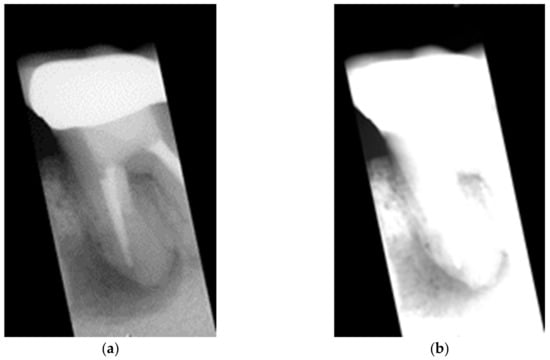

2.2. Enhancing Lesion

2.2.1. Grayscale Image

2.2.2. Gaussian High Pass Filter

2.2.3. Lesion Heightened